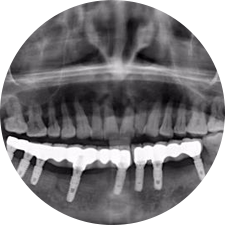

口腔種植是將人工牙根通過手術(shù)植入牙骨內(nèi),獲得牙槽骨牢固的支持,通過特殊的裝置和方式連接牙修復(fù)體,獲得與天然牙功能、結(jié)構(gòu)以及美觀相似的效果。

河北惟德口腔醫(yī)院擁有國內(nèi)豐富的半口/全口、即刻負重種植案例,十八年案例跟蹤分析,總結(jié)梳理出的各種不同類型的種植案例,Nobel種植體系針對半口/全口缺牙患者,通過4-8顆種植體可快速達到牙齒重建,不僅植入種植體較少,節(jié)省費用,手術(shù)時間更短。

術(shù)前患者CBCT口掃1:1三維重建,模擬手術(shù)過程及預(yù)測術(shù)后治療效果,確定每顆植體植入的適合的種植位點、深度及角度,有效避免損傷頜骨重要解剖結(jié)構(gòu),提高手術(shù)準確度與安全性。

Noble口腔種植體系基本不受年齡限制,適用于缺牙修復(fù),也適用于牙槽骨萎縮、骨質(zhì)疏松、高血壓、糖尿病、超高齡的患者,即種即用,只需少量微小種植體,便可輕松微痛快速重建全口咬合,特殊力學設(shè)計,針對許多年紀較大,骨質(zhì)條件差,身體耐受力差的缺牙老人也能完成“即種即用”,受到廣泛好評。

惟德口腔種植體系是以患者感受為中心,取代傳統(tǒng)種植牙手術(shù)需要翻瓣、打孔、縫合,術(shù)前、術(shù)中、術(shù)后的繁復(fù)流程,采用3D導(dǎo)航微創(chuàng)準確種植技術(shù),通過數(shù)字化CAD/CAM掃描技術(shù)獲得缺牙患者口腔數(shù)據(jù),以數(shù)據(jù)為基礎(chǔ)重建口腔模型進行模擬種植。

術(shù)前將患者口內(nèi)的CBCT數(shù)據(jù)及咬合關(guān)系上傳到計算機中,建立1:1三維重建,模擬手術(shù)過程及預(yù)測術(shù)后治療效果,找出較佳種植位點、深度及角度,獲取實際種植體在頜骨內(nèi)的具體三維位置,有效避免損傷頜骨重要解剖結(jié)構(gòu),大大降低手術(shù)風險,提升種植成功率。